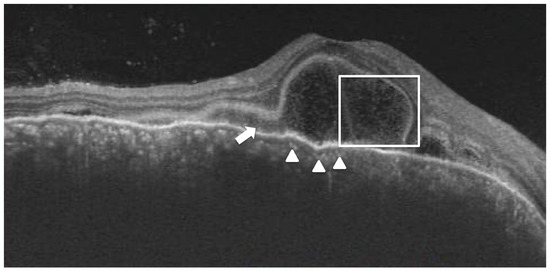

Subretinal hyperreflective dots were defined as hyperreflective dots below the neurosensory retina and over the RPE without associated back shadowing (Figure 3B). Choroidal hyperreflective dots were defined as circumscribed dots within the choroid seen on an OCT scan having equal or higher reflectivity than the RPE band (Figure 4). Bacillary layer detachment was defined as a split of the neurosensory retina at the level of the myoid zone in the photoreceptor layer (Figure 4). RPE vacuolations were defined as hypo reflective cavities within the RPE (Figure 3A).

Figure 4. A 32-year-old lady with a diagnosis of acute Vogt-Koyanagi-Harada disease. The right eye shows bacillary layer detachment (white box) with subretinal hyperreflective material (white arrow) and choroidal hyperreflective dots (white arrowhead).